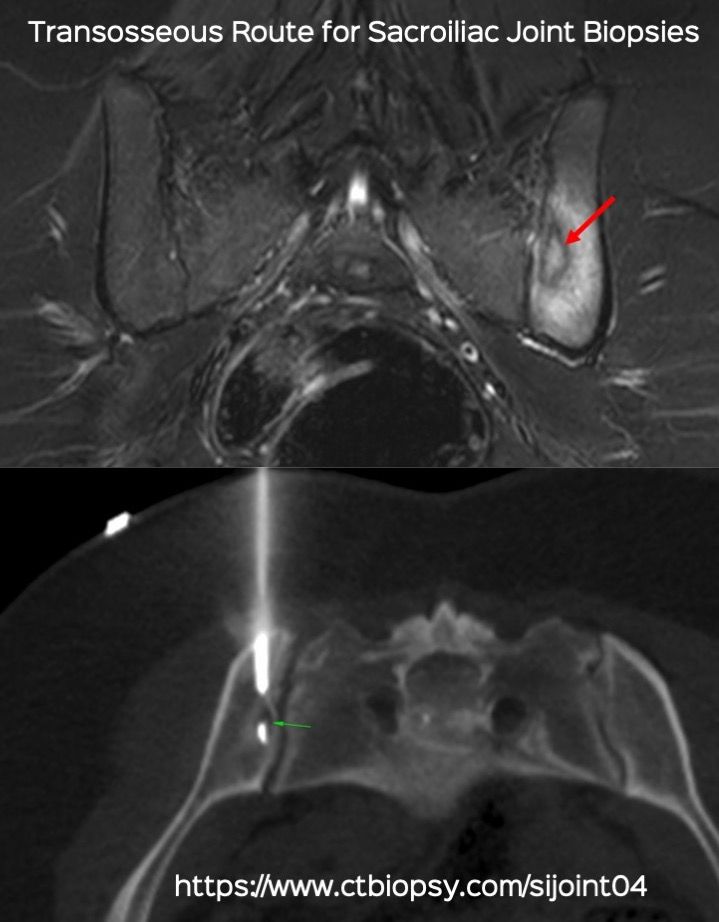

Case 84: Transosseous Route for Sacroiliac Joint Biopsy